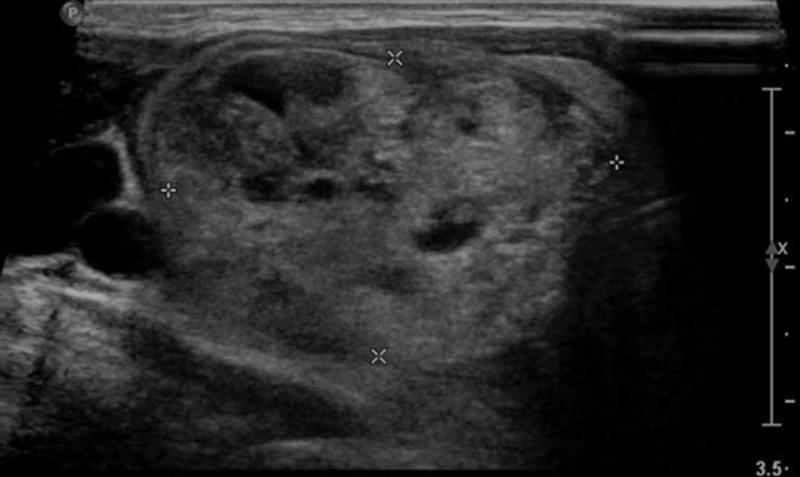

The presentation of atherosclerosis with concomitant hyperthyroidism is not uncommon. Hyperthyroidism predisposes to worse cardiovascular pathologies like systolic hypertension, atrial fibrillation, and hypercoagulability. Drug-eluting stents, on the other hand, have emerged as a miracle treatment choice for patients having atherogenic conditions. They have the highest success rates when it comes to minimizing in-stent restenosis (ISR) during short-term follow-up. There is scarce literature that assesses the correlation of multinodular goiter (MNG) to ISR, especially in Pakistan, and thus any probable association between the two is left untouched. We report a case of a 57-year-old female who is a known hyperthyroid with a massive MNG, presenting with worsening chest pain. She had undergone sirolimus-eluting stent (SES) implantation in left anterior descending artery (LAD) six months back. Cardiac catheterization confirmed restenosis of the SES in the LAD, along with the occlusion of left circumflex and right coronary artery, accompanied by grade I diastolic dysfunction and mild aortic regurgitation on echocardiography.

动脉粥样硬化合并甲状腺功能亢进的情况并不少见。甲状腺功能亢进易引发更严重的心血管疾病,如收缩期高血压、心房颤动和高凝状态。另一方面,药物洗脱支架已成为患有动脉粥样硬化疾病患者的一种神奇治疗选择。在短期随访中,它们在最小化支架内再狭窄(ISR)方面成功率最高。评估多结节性甲状腺肿(MNG)与ISR之间相关性的文献很少,尤其是在巴基斯坦,因此两者之间的任何可能关联都未得到探讨。我们报告一例57岁女性病例,她是一名已知的甲状腺功能亢进患者,患有巨大的MNG,出现胸痛加重症状。她六个月前在左前降支(LAD)植入了西罗莫司洗脱支架(SES)。心脏导管检查证实LAD处的SES再狭窄,同时左旋支和右冠状动脉闭塞,超声心动图显示伴有I级舒张功能障碍和轻度主动脉瓣反流。